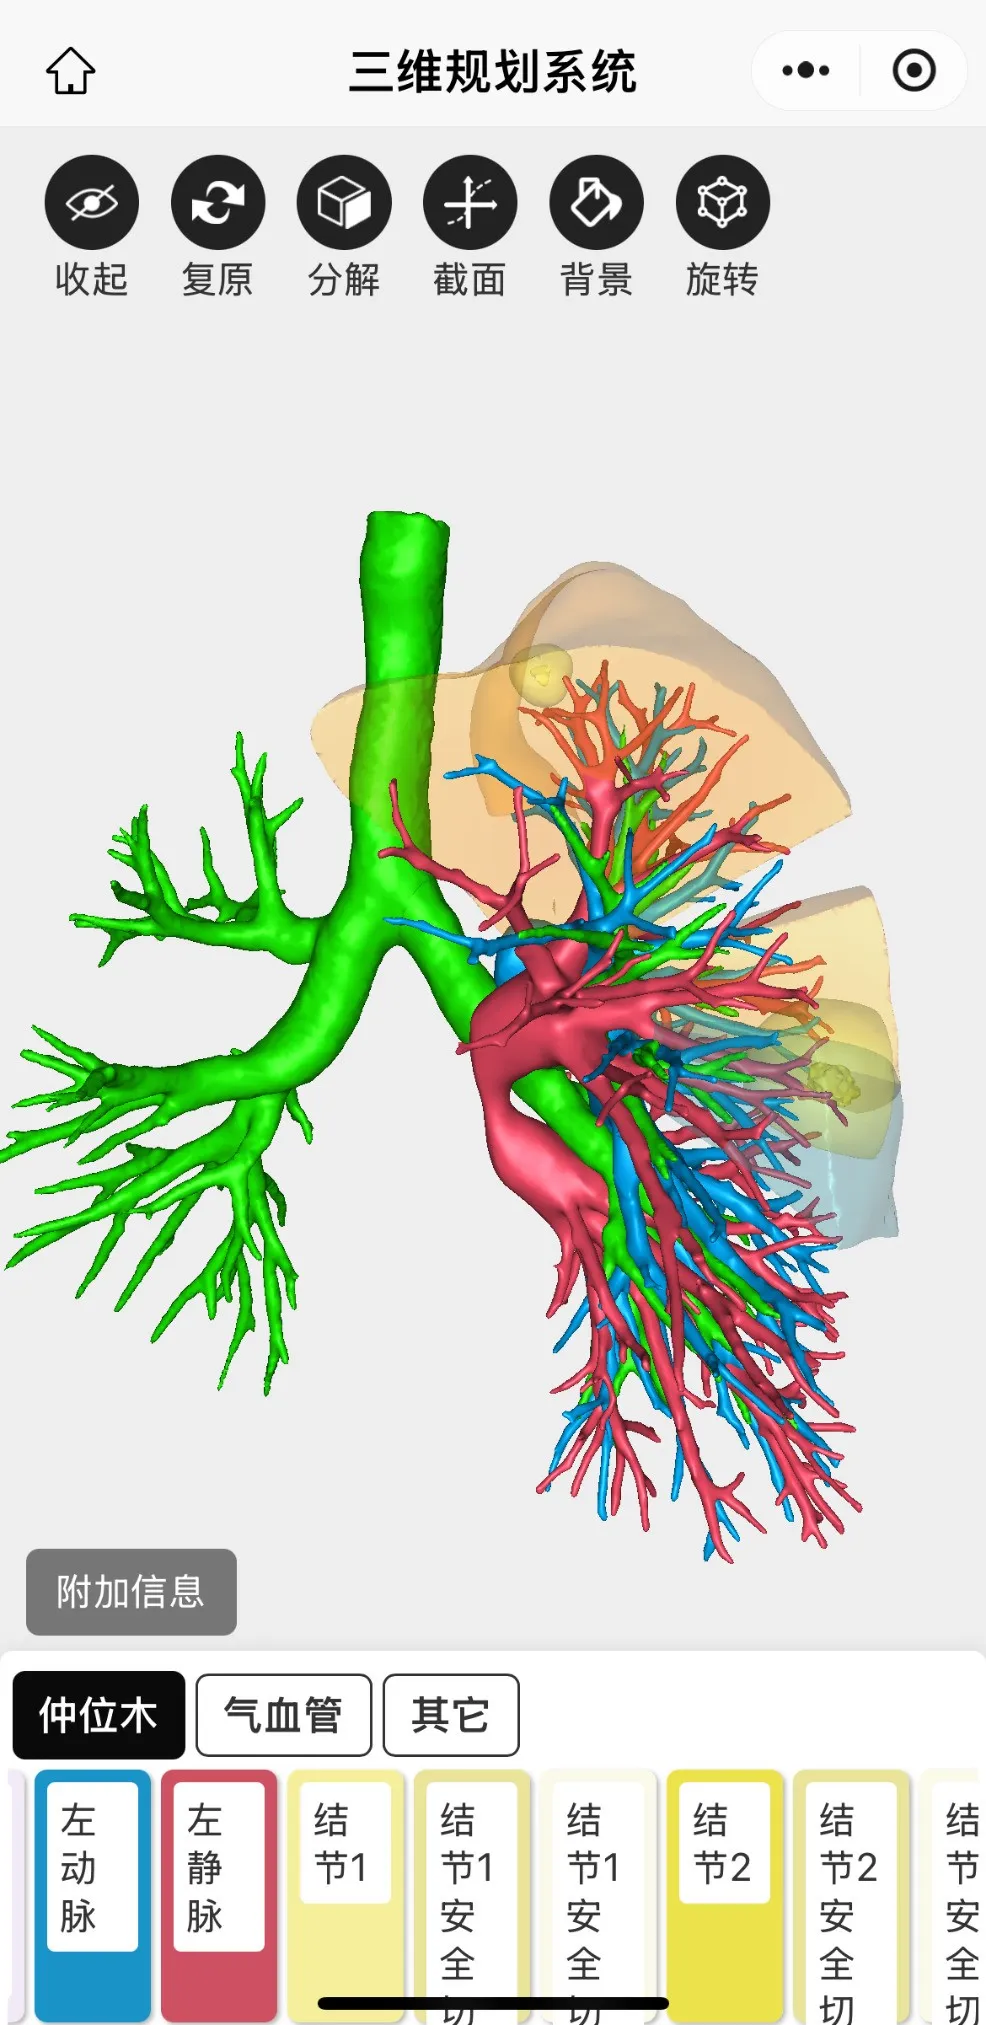

三維重建後圖片如下

最終為患者行左肺上葉S1+2c與S4a聯合亞段切除及S1+2a段(duàn)楔形切除術。患者術後2天出院,恢(huī)複良好,手術後對肺功能無影(yǐng)響。結節1病理為(wéi)原位癌,結(jié)節2為良好病灶。患者對91麻豆视频(men)手術方(fāng)案非(fēi)常滿意,痊(quán)愈出院。

三維重建輔助下肺癌精準肺段切除術,是一種先進的肺癌手術方式。主要(yào)借助CT影(yǐng)像數據,利(lì)用計(jì)算機技術對肺部、血管及支氣管等進行三維(wéi)立(lì)體建模,清晰呈現肺部解剖結構。優勢在於,醫生能精準定位腫瘤位置和(hé)邊界,規劃手(shǒu)術路徑,準確切除包含腫瘤的肺段,保留更多健康肺組織(zhī),提升患者(zhě)術後(hòu)肺功能和生活質量。同時減少術中出血(xuè)、降低損傷周圍組織風險。